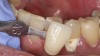

Case Study 2

A 45-year old male patient presented with tooth No. 21 that had an intermediate restorative material (IRM) restoration on the facial aspect after a pulpotomy due to a carious lesion into the pulp from the facial (Figure 7 and Figure 8). The patient had root canal therapy and a post-and-core buildup placed on No. 21 before the crown. The patient was involved in the decision-making for the enamel shade on No. 21. He wanted to make sure that the clinicians did not match No. 21 with No. 20 because he felt the shade on No. 20 was too dark. Instead, the patient wanted to match the new ZLS that had been planned on No. 21 with the natural shade of No. 23 and No. 24. The facial and occlusal views revealed the obvious differences in shade between No. 21 and No. 20. The plan was to use pressable ZLS due to its esthetics, shade-matching abilities, strength, and ease of finishing, so it was decided to involve the dental laboratory technician with the shade-taking process. In planning the discussion with the laboratory technician, the author felt that the best shade would be a Vita A3.5. However, because the laboratory technician worked about 90 minutes away, the author wanted to get his input on the shade by sending him several photographs using the shade the author felt tooth No. 21 was (ie, Vita A3.5) plus shades that were close (ie, Vita A3 and Vita A4). Laboratory technicians are more familiar with shading techniques and may see something that the dentist did not see in the surrounding teeth. This is important when using ZLS to take full advantage of the blending ability that this material displays. The final crown displayed a vibrant match of hue and chroma (Figure 9 through Figure 13).